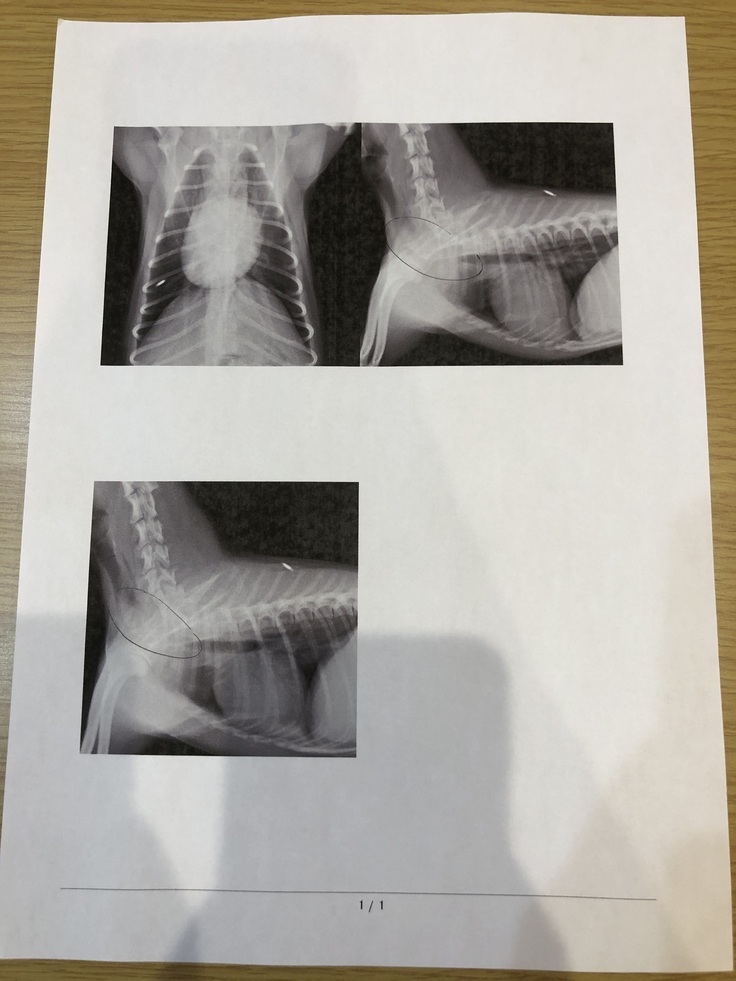

↑実際のレントゲンの写真です。

骨と重なり分かりにくい状態となっていますが気管のほとんどが潰れている状態です。

詳しく検査をする為にCTと内視鏡検査をする予定でしたが、命に関わるとの事で検査もできない状態です。